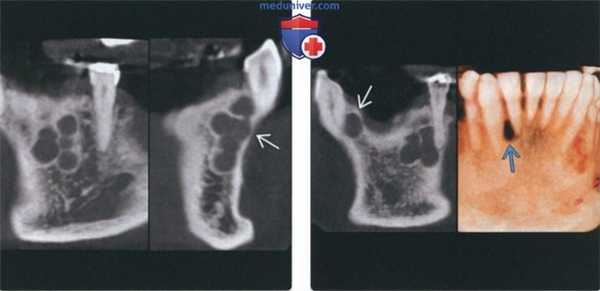

(Слева) На корональной КЛКТ (слева) у этого же пациента определяются небольшие округлые рентгенонегативные участки, хорошо отграниченные кортикальной пластинкой. На КЛКТ (профильный срез) справа определяется истончение щечной кортикальной пластинки в отсутствие вздутия. Эти признаки могут быть полезны при дифференциальной диагностике с амелобластомой.

(Справа) На корональной КЛКТ (слева) у этого же пациента определяется еще одно однокамерное образование в передних отделах нижней челюсти справа. На 3D КЛКТ (справа) определяется типичная боковая периодонтальная киста в виде «слезы» между корнями зубов.